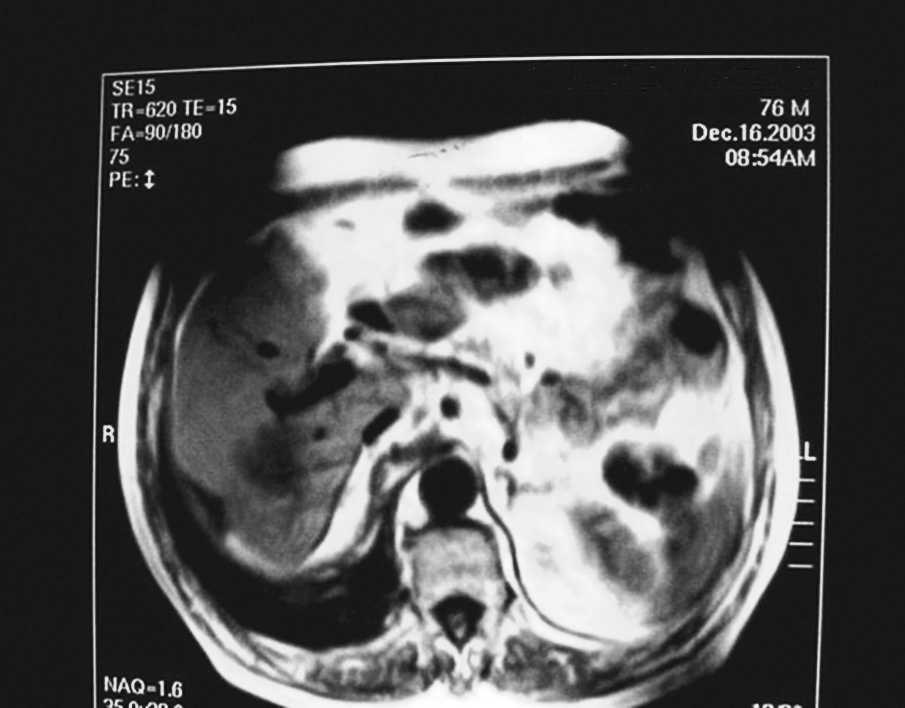

Caso 2. Mujer de 60 años con dolor y tumor abdominal, cuya tomografía computarizada abdominal mostraba una masa que nacía en el segmento 5 del hígado cirrótico y alcanzaba la cresta ilíaca (fig. 2). Se realizó quimioembolización y resección quirúrgica, pero falleció en el postoperatorio inmediato.

Fig. 2. Paciente de sexo femenino, de 60 años, con cirrosis por el virus de la hepatitis C. Carcinoma hepatocelular pedunculado, segmento 5.